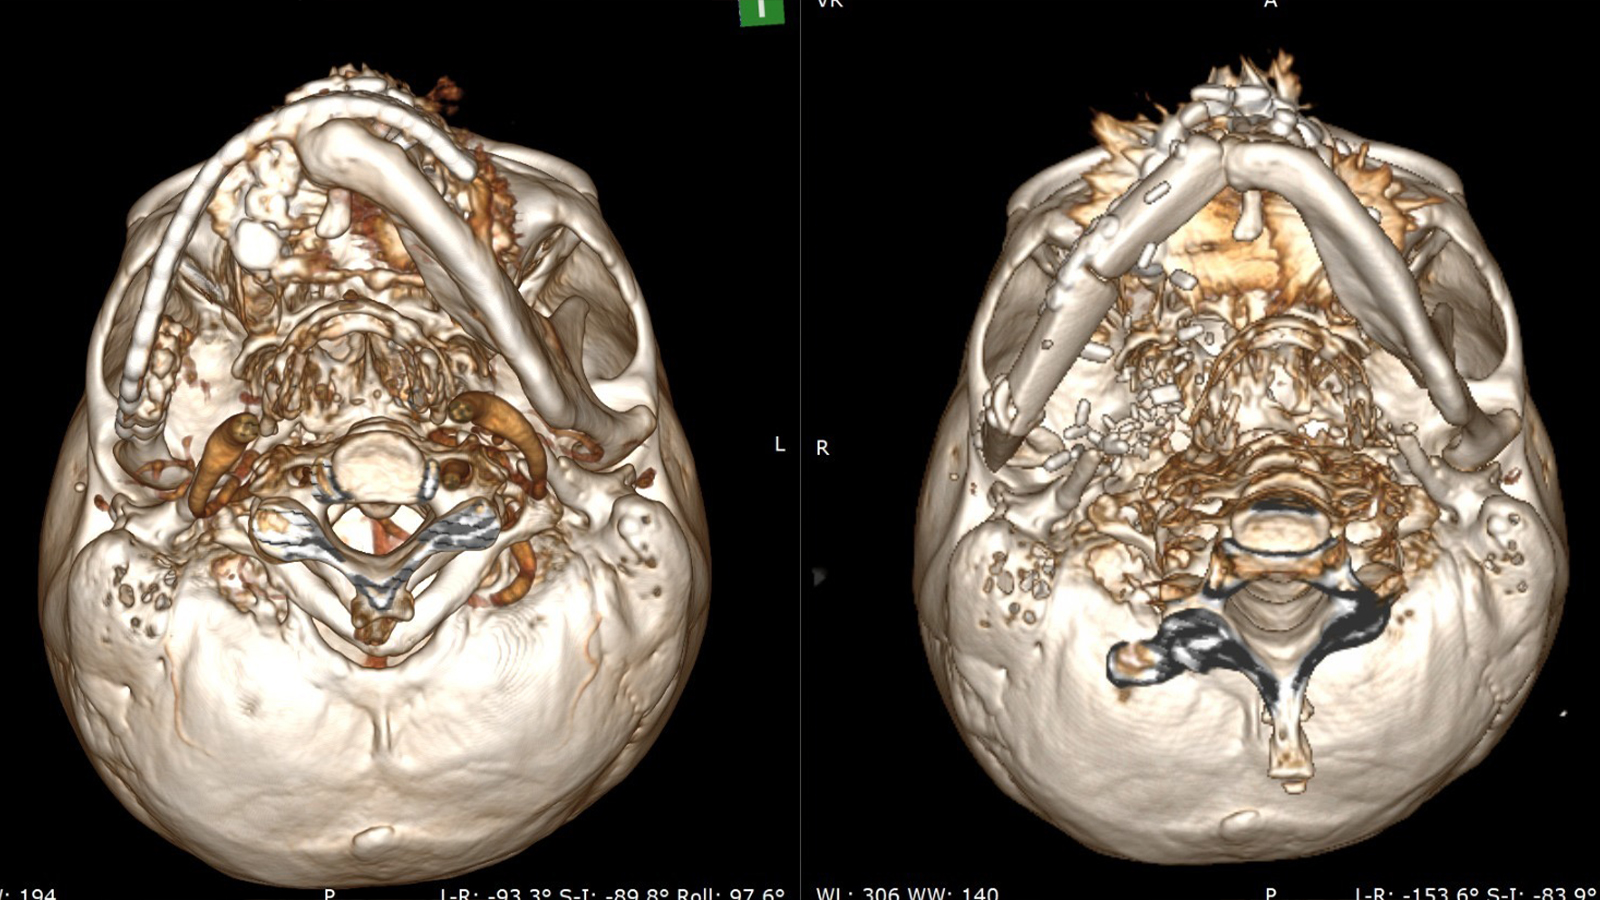

Bir il yarım əvvəl pasiyentə baş-boyun nahiyəsində yerləşən geniş yayılmış bədxassəli törəmə səbəbilə aşağı çənənin yarısı çıxarılmış və onun yerinə titan konstruksiya yerləşdirilib. Müasir tibbi texnologiyaların tətbiqi sayəsində həyata keçirilən son əməliyyat zamanı əvvəlcədən qoyulmuş titan lövhə çıxarılıb, aşağı çənənin yarısı pasiyentin öz sümüyü — fibula (incik sümüyü) vasitəsilə yenidən qurulub.

Mikrocərrahi üsulla icra olunan rekonstruksiya zamanı sümük strukturu pasiyentin ayağından götürülərək üz nahiyəsinə transplantasiya edilib və damarlar yüksək dəqiqliklə birləşdirilib. Bu yanaşma onkoloji əməliyyat nəticəsində itirilmiş üz nahiyəsinin həm funksional, həm də estetik baxımdan bərpasına imkan verir. Mütəxəssislərin sözlərinə görə, gələcək mərhələdə bərpa olunmuş sümüyə dental implantların yerləşdirilməsi planlaşdırılır ki, bu da pasiyentin həyat keyfiyyətinin tam bərpasına şərait yaradacaq.